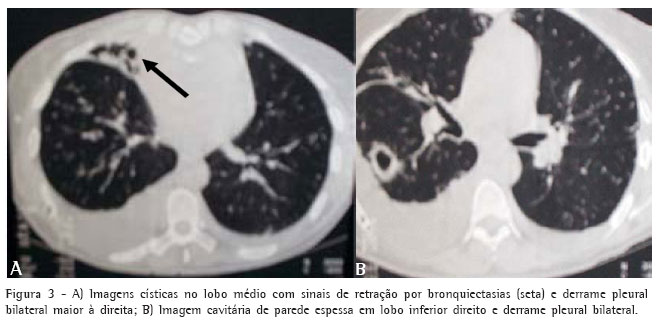

Trouxe consigo os seguintes exames: ultra-som abdominal, com leve hepatomegalia inespecífica, derrame pleural bilateral e microlitíase em vesícula biliar; e tomografia computadorizada do tórax, que apresentava derrame pleural bilateral, dilatações brônquicas císticas no lobo médio e presença de imagem cavitária no segmento apical do lobo inferior direito (Figuras 3A e 3B).

O caso aqui apresentado tem achados que merecem destaque: a tríade é completa e com presença de sinusite crônica e bronquiectasias evidentes à tomografia computadorizada de alta resolução; em julho de 2003, a paciente apresentou tuberculose pulmonar com imagem cavitária à tomografia computadorizada do tórax e exame de bacilo álcool-acidorresistente positivo no exame de escarro; uma irmã faleceu com quadro clínico semelhante; a paciente possui um irmão vivo e portador da tríade completa; a pesquisa de quilotórax como causa do derrame pleural foi negativa; e não houve achado de derrame pericárdico ou peritoneal.